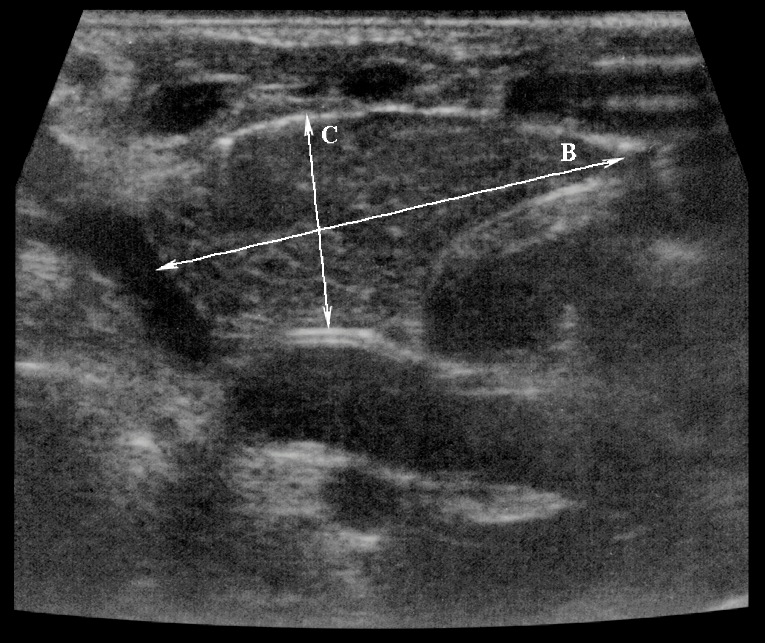

Тимомегалия: что это такое и как проявляется